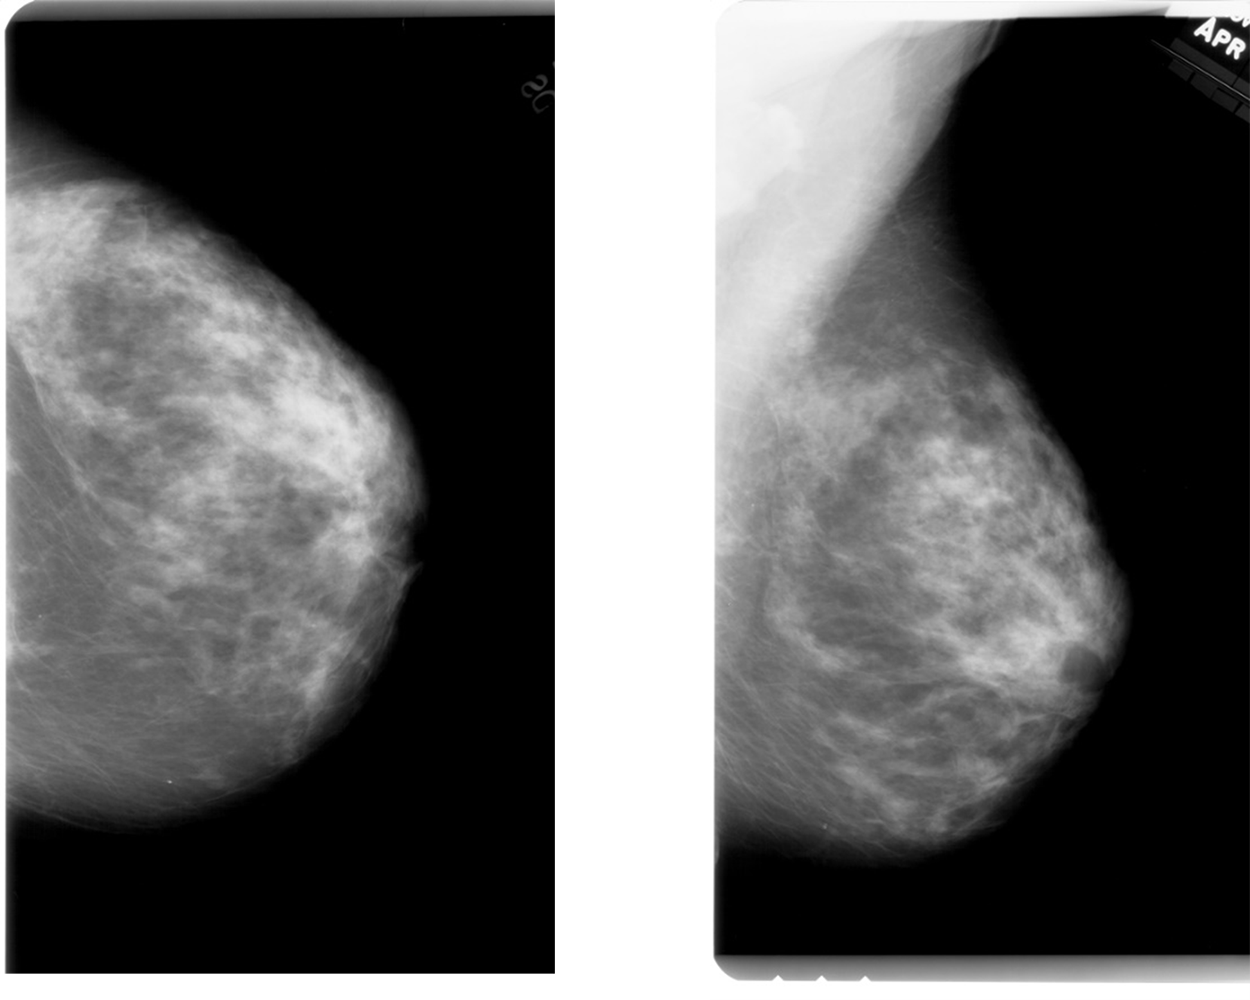

Figura 2 Mamografii ale aceluiași sân din două unghiuri diferite: Cranial - caudal (stânga), Mediolateral-oblig (dreapta)

Primul și poate cel mai important pas în dezvoltarea unui algoritm de inteligență artificială este pre-procesarea datelor de intrare. Mamografiile și măștile sunt disponibile în format DICOM, la o rezoluție de peste 3000 pixeli. Suplimentar, avem la dispoziție și alte informații: ID-ul pacientului, tipul de vedere al imaginii, pe ce sân este prezentă tumoarea, ID-ul tumorii, patologia (benign sau malign) sau căile relative către mamografii și măști. Tipul de vedere reprezintă unghiul din care a fost făcută mamografia: cranial-caudal (CC) sau mediolateral-oblig (MLO). Setul de date este împărțit în patru fișiere de tip .csv după destinația datelor (antrenare și testare), respectiv tipul tumorii (mase sau calcifieri). Pentru o mai ușoară organizare și manipulare a datelor, acestea au fost concatenate într-unul singur. Toți acești pași pot fi refăcuți cu ajutorul Jupyter notebookului data_analysis/data_analysis.ipynb.